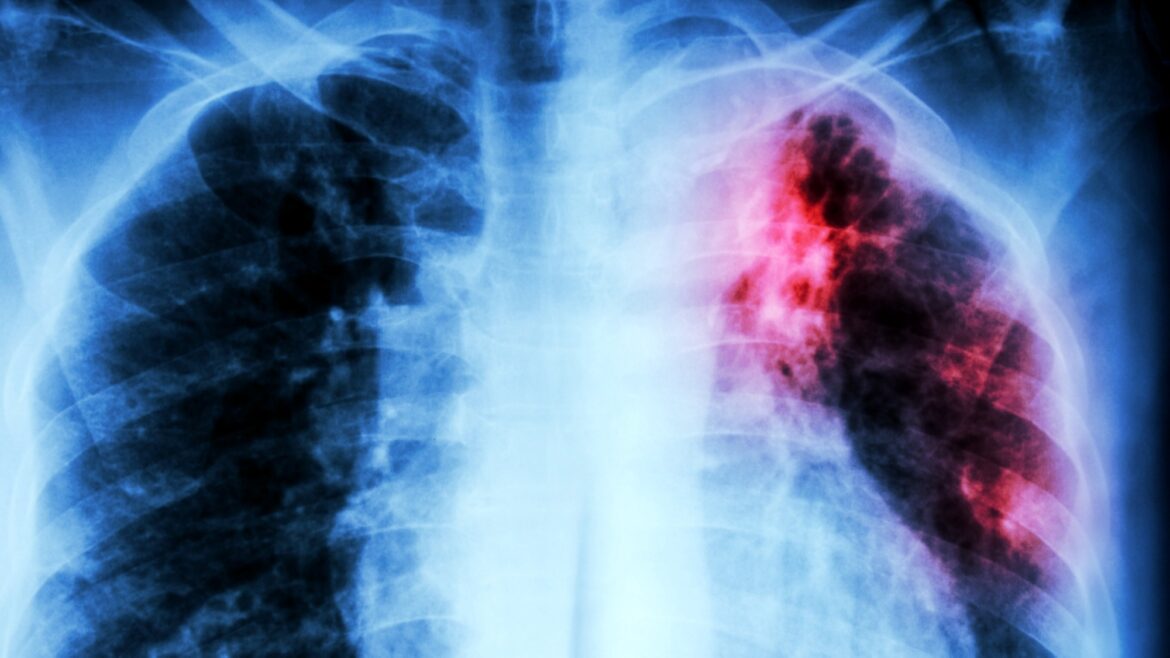

كشفت دراسة حديثة أُجريت بجامعة “سيدني” الأسترالية، عن آلية حيوية دقيقة داخل بكتيريا Mycobacterium tuberculosis، المسببة لمرض السل، قد تمثل هدفًا علاجيًا جديدًا، حيث ركّز الباحثون على نظام داخلي مسؤول عن تنظيم جودة البروتينات والحفاظ على توازنها داخل الخلية.تحديد 3 مركبات تستهدف مُسبّبات العدوىوأوضحت الدراسة أن البكتيريا تعتمد على نظام يُعرف بـ”البروتياز” (Protease system)، وتحديدًا مركّب ClpC1–ClpP، الذي يعمل على تفكيك البروتينات التالفة وإعادة تدويرها، ما يمكّن البكتيريا من البقاء داخل الخلايا المناعية ومقاومة الظروف القاسية التي تواجهها أثناء العدوى.وبيّنت النتائج المنشورة بمجلة “Nature Communications” العلمية، أن الباحثين حدّدوا 3 مركبات تجريبية قادرة على استهداف هذا النظام الحيوي، حيث تؤدي إلى تعطيله بشكل غير طبيعي، ما يتسبب في تراكم البروتينات التالفة داخل البكتيريا، وإحداث خلل سام يضعفها ويمنعها من الاستمرار أو التكاثر.وأشار الفريق العلمي إلى أن هذه الآلية تختلف عن عمل المضادات الحيوية التقليدية، ما يجعلها خيارًا واعدًا لمواجهة السلالات المقاومة للأدوية، خاصة في ظل استمرار المرض كأحد أكثر مسببات الوفاة عالميًا، مع تسجيل أكثر من مليون حالة وفاة سنويًا وفق تقديرات صحية حديثة.